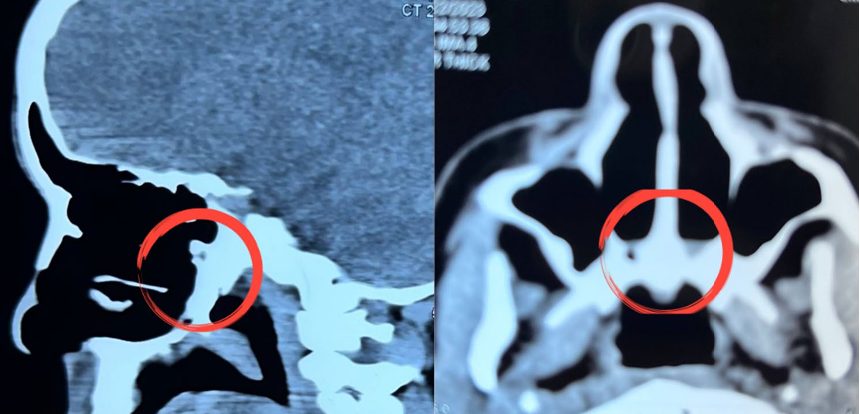

She denied any history of previous nasal trauma or nasal surgery. On examination, the patient has associated anomalies such as an arched palate, prognathism, disturbed alveolar arches, and mal occlusion class III. On endoscopic examination, the nasal septum was seen to be located at midline,

rudimentary middle turbinate, and bilateral posterior choanal plates were atretic . Computed Tomography (CT) showed Bilateral CA. Upon this, the patient was prepared for nasal surgery to open the posterior choana and establish the nasal passages.